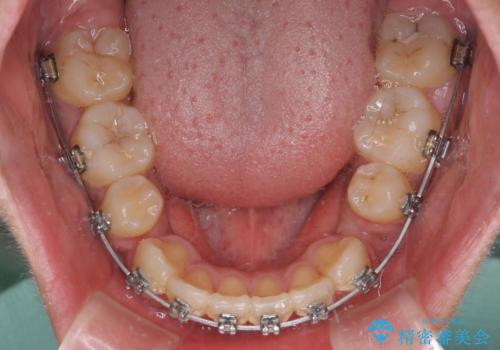

膨らんだ口元 ワイヤー装置での抜歯矯正

- メタルブラケット

上下前歯が著しく前突している状態であったので、上下左右の第1小臼歯4本を抜歯し、ワイヤー装置にて矯正治療を行うこととしました。

受験勉強と重なり、舌のトレーニングが十分に行えず、高校生としてはやや長期間の治療となりました。